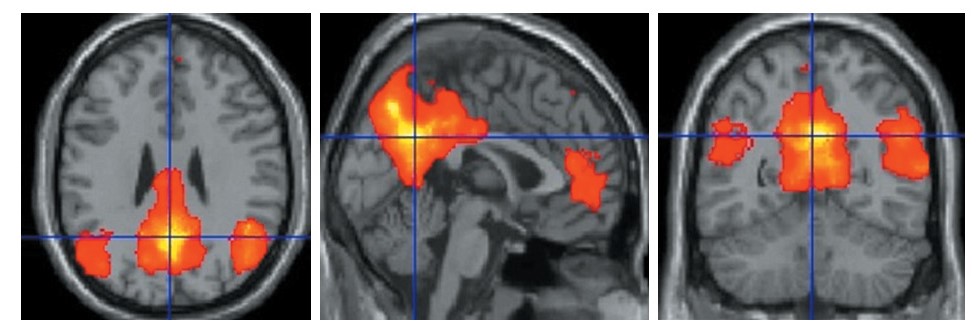

Одним из основных инструментов, позволяющих оценить корковую нейрональную активность, является функциональная МРТ (фМРТ), представляющая собой разновидность МРТ, которая позволяет визуализировать зоны нейрональной активации (НА) в ответ на предъявляемые стимулы. В основе метода лежат 2 основных понятия: нейроваскулярное взаимодействие и BOLD-контраст (Blood-Oxygenation-Level-Dependment – контраст, зависящий от уровня оксигенации крови). Под нейроваскулярным взаимодействием понимается взаимосвязь между НА и региональным кровотоком. В ответ на определенное воздействие в отдельных участках ГМ происходит повышение соотношения окси- и дезоксигемоглобина, приводящее к усилению интенсивности сигнала на серии Т2-взвешенных изображений. Методика позволяет оценить распределение зон активации ГМ и провести корреляцию между анатомической локализацией и функциональной активностью коры ГМ [6].

Особой разновидностью фМРТ является фМРТ покоя. Интерес представляет изучение сети пассивного режима работы ГМ. Во время проведения фМРТ покоя больному не предъявляется стимул. Полагают, что низкочастотные колебания BOLD-сигнала в состоянии покоя отражают базальную активность нейронов, а анатомически удаленные друг от друга зоны активации со сходными частотными и временными характеристиками сигнала считаются функционально взаимосвязанными. Данная связь называется функциональной коннективностью. Различные паттерны НА, обладающие индивидуальными пространственными и частотными характеристиками, формируют сети покоя. Наиболее стабильно выявляется сеть пассивного режима работы ГМ [7], которая состоит из функционально связанных между собой участков ГМ, включающих поясные извилины и задние отделы предклинья, средние и нижние височные извилины, надкраевые и угловые извилины, верхние и средние лобные извилины, медиальную префронтальную и фронтальную кору (рис. 1).

Рис. 1. фМРТ покоя. Групповая карта спонтанной нейрональной активности ГМ в группе пациентов с ИБС. Собственное наблюдение.

Fig. 1. Resting fMRI. Group map of spontaneous neuronal activity of the brain in the group of patients with coronary artery disease. Author’s observation.